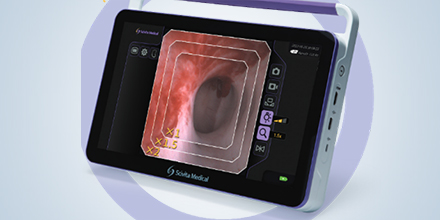

Single Use Bronchoscopes SBV and Portable Solutions HDVS-S300

Full HD Visualization in a single use Procedure

Superior optical performance, accurately shows subtle details of the mucosal in the bronchial tree among a large selection of bronchoscopes with different external diameters. Image comes live within seconds to the portable monitor, to which data are stored and can be easily transported, providing convenience even in OR or ICU areas